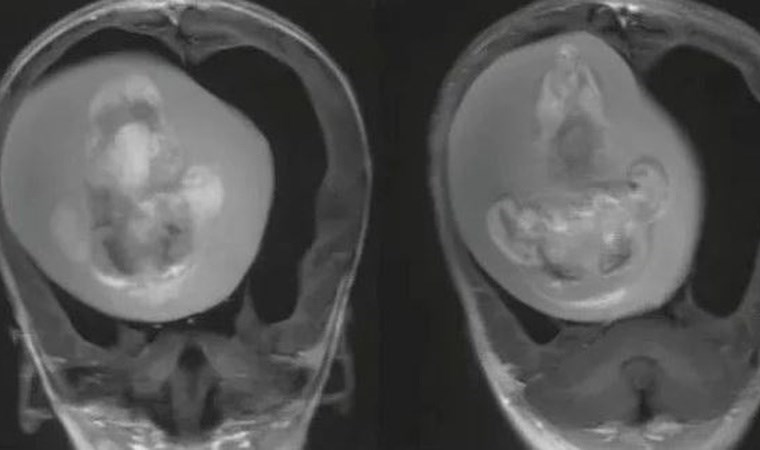

Bebeğin kafatasının beklenenden geniş olduğu ve hastaneye motor becerilerindeki sorunlar nedeniyle getirildiği bildirildi. Motor beceriler; emekleme, ayakta durma, yürüme, koşma, salınım, dönme, yuvarlanma, zıplama ve denge kurma gibi hareketlerin gerçekleştirilmesini sağlıyor. Bebeğin kafatasını çeşitli görüntüleme yöntemleriyle inceleyen araştırmacılar, beyninin sıkıştığını ve sıvı birikimi oluştuğunu tespit etti.

Independent Türkçe’nin aktardığına göre, ileri incelemeler, bebeğin aslında anne karnındayken bir ikiz kardeşi olduğunu ama ikinci bebeğin yeterince gelişemeyerek kardeşinin kafatasının içine sıkıştığını ortaya çıkardı. Doğmamış ikiz kardeşin, doktorların deyimiyle “fetiform kitlenin” üst uzuvları ve hatta parmak benzeri çıkıntıları bile gelişmiş gibi görünüyordu.

Ancak fetüsün gövdesi ve diğer kısımları yeterince gelişememişti. Sonuçta yeterince gelişemeyen bu embriyo diğeri tarafından içerilmişti.

Böylece gelişmemiş olan bebek, diğerinin kafatasına sıkışmıştı. Hazırlanan vaka raporu son derece kısa olduğu için bir yaşındaki kız çocuğunun durumunun ameliyattan sonra nasıl seyrettiği belli değil.